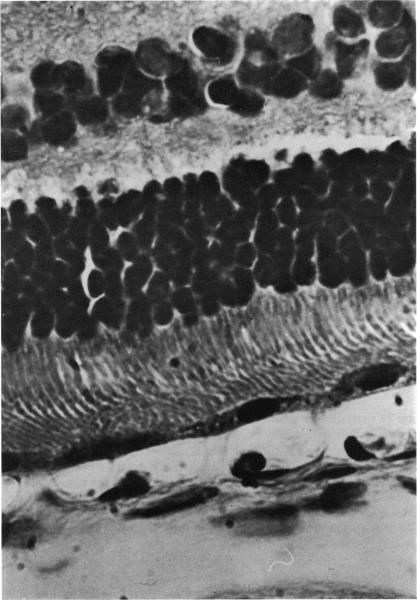

Reaction of the rabbit retinal pigment ipithelium to systemic lead poisoning.

Trans Am Ophthalmol Soc. 1974;72:404-47.